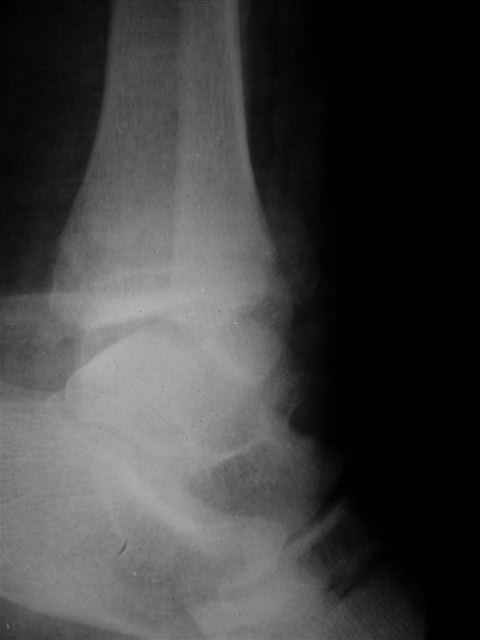

> Если Вас не затруднит, пришлите, пожалуйста, рентгенограммы. Я

> интересуюсь тактикой лечения повреждений голеностопного сустава.

Ничего сверхъестественного, но если есть интерес, то в понедельник пересниму Рг-граммы и отправлю.

Уважаемый Иван,

Я предупреждал, что ничего сверхъестественного. Каюсь, что одна из спиц прошла несколько дальше, чем нужно было, но главное - перелом стабилизирован и больной работает суставом в полном объёме, несмотря на представленную раннее травму коленного сустава.